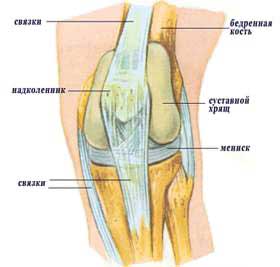

Анатомические изображения менисков и коленного сустава